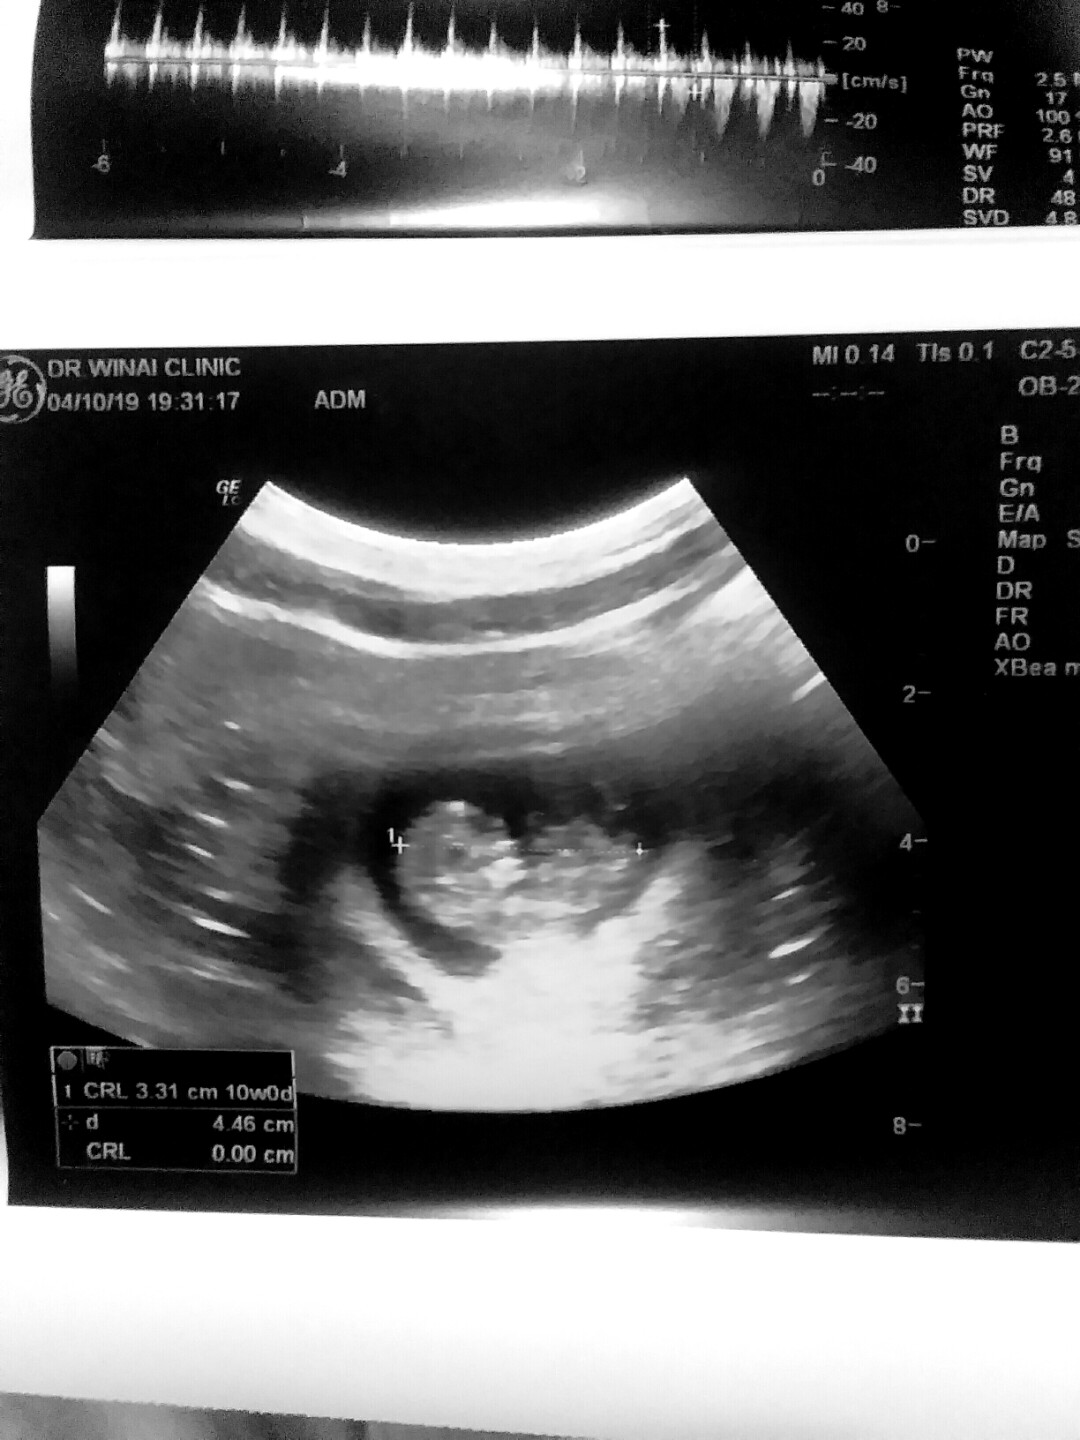

ไปซาวมาเมื่อวาน 10w4d

10w4d ตอนนี้20w4d